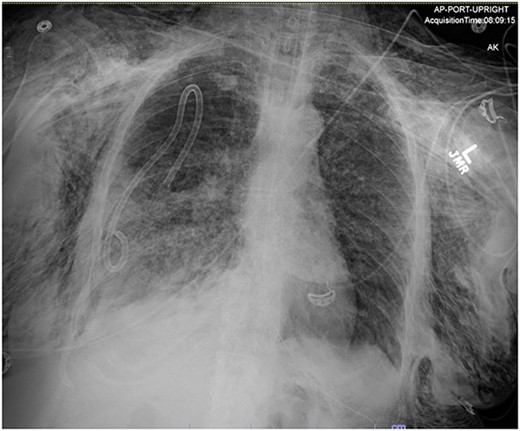

On Hospital Day 2, an interval CXR showed continued resolution of the right-sided pneumothorax but worsening subcutaneous emphysema of the bilateral chest wall and pneumoperitoneum (Fig. 3). Surgical consultation was sought, leading to diagnostic laparoscopy. In the abdomen, emphysematous changes within the gastrohepatic ligament and omental adhesions to the anterior abdominal wall were visualized (Figs 5 and 6). Laparoscopic exploration revealed no diaphragmatic injury or perforated viscera but identified emphysematous changes throughout the preperitoneal space, small and large bowel mesentery, and right paracolic gutter (Figs 7 and 8). Immediate post-op CXR no longer showed evidence of pneumoperitoneum (Fig. 4). The patient was transferred back to the ICU and extubated after three days on Day 5. After the removal of chest tube and transfer to a medical floor on Day 8, the patient developed aspiration pneumonia that was treated with antibiotics. She was discharged on Day 15.

Post-operative chest radiograph showing increased diffuse subcutaneous emphysema in chest, lower neck and upper left abdominal wall. Previously demonstrated pneumoperitoneum is not visualized on the current film.